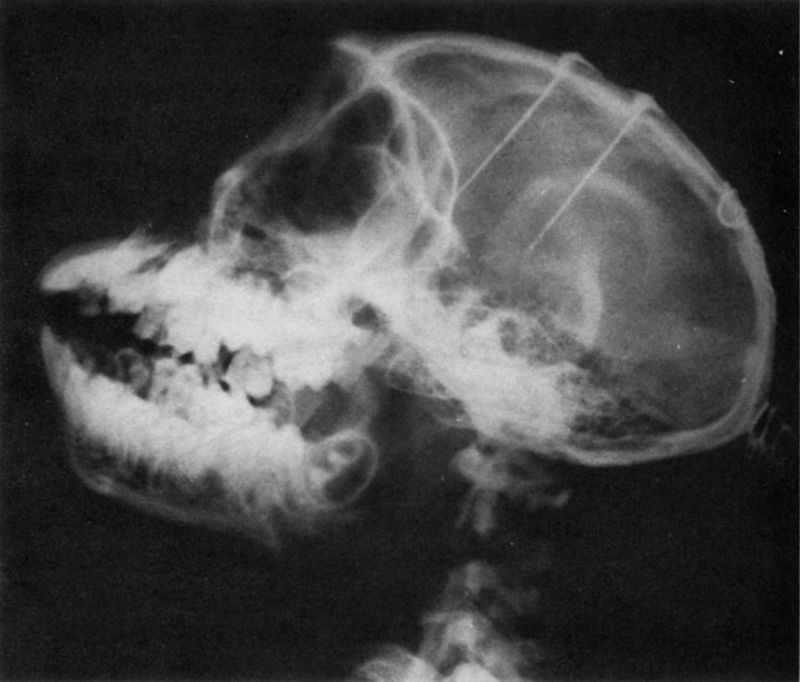

The methodological breakthrough which made it possible to study the brain of behaving animals came in the 1930s when W.R. Hess (106) devised a procedure to implant very fine wires within the brain of anesthetized cats. After the effects of anesthesia had disappeared, the relatively free and normal animal could be electrically stimulated by connecting long leads to the terminals of the implanted electrodes. This procedure was refined in the early 1950s (47, 49) by reducing the size of the electrodes while increasing the number of intracerebral contacts and using aseptic precautions during implantation. Surgical accuracy in reaching chosen cerebral targets was also improved by means of micromanipulators and a precise system of anatomical coordinates which made it possible to reach similar structures in different subjects. Using biologically inert materials such as gold, platinum, or stainless steel wires insulated with teflon allows the electrodes to be left inside of the brain indefinitely. A diagram of the cerebral implantation of one assembly of seven contacts is shown in Figure I and the X ray of the head of a monkey after implantation is seen in Figure 2. Through a small opening in the skull, the shaft is introduced down to a predetermined depth and is secured with dental cement at the point where it passes through the skull. Then the upper portion of the shaft is bent over the bone surface and secured again a short distance away, and the terminal socket is exteriorized on the head. Each contact of the socket corresponds to a determined point in the depth of the brain which is accessible merely by plugging in a connector, a procedure as simple as connecting any electrical appliance to a wall outlet. This technique has been used for ESB in thousands of animals in

Page 82

Page 83

many laboratories around the world, and there is ample experience of its efficiency, accuracy, and safety, resolving the initial skepticism that introduction of wires into the brain would be technically difficult, dangerous for the subject, and grossly disruptive of normal functions. It is true that implantation of electrodes destroys neurons along the path of penetration, breaking capillary vessels and later producing a local reaction involving the formation of a thin fibrotic capsule along the implantation tract. It has been proven, however, that local hemorrhage is neglible and that because of the well-known functional redundancy of neural tissue with abundance of duplication in its circuits, the destruction of a relatively small group of neurons